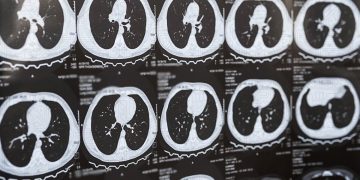

Há novas ferramentas de IA para gerar dados sintéticos no diagnóstico do cancro do pulmão e o INESC TEC está a desenvolvê-las